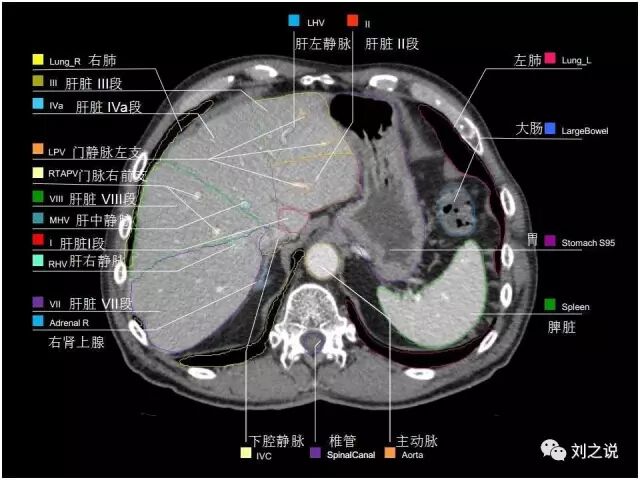

【解剖】高清实用 腹部CT断层

参考RTOG共识和3D-body解剖。